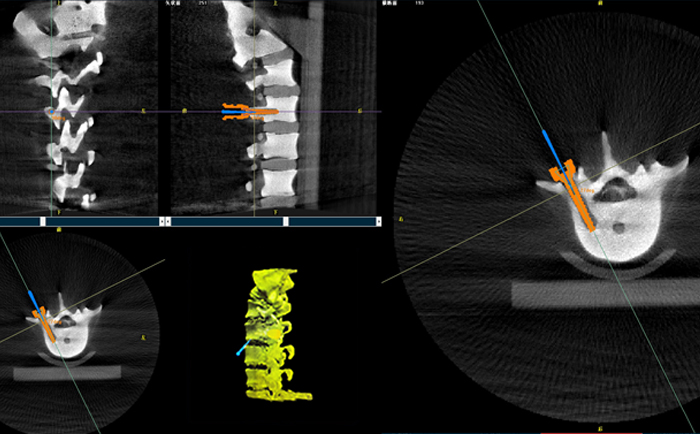

在一台机器人辅助下的脊柱手术中,使用三维C形臂与机器人匹配,仅15秒左右就能获得患者病变脊柱部位的高清3D图像,机器人辅助手术可准确定位病变部位、置入椎弓根螺钉位置等。

目前脊柱外科应用最广泛的还是机器人辅助置入椎弓根螺钉。主刀大夫可以通过该3D图像确定手术中椎弓根螺钉的进钉点、置钉方向以及置钉深度。紧接着,在机器人手术系统的导航下,该机械手臂能够准确移动到定位椎弓根螺钉等置钉位置,医生只需要在置钉部位切开一个1cm切口,沿着机械臂所指方向钻入导针,并沿导针按置入椎弓根即可,从而使椎弓根螺钉能够以最理想化的方式打入,保证患者的安全和手术有效性。